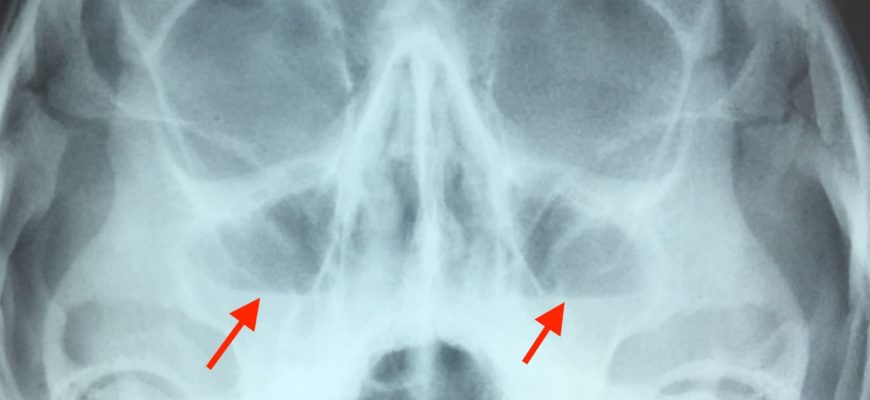

Гайморит – распространенное воспалительное заболевание носа, характеризующееся поражением слизистой оболочки околоносовой пазухи. Клинические проявления гайморита могут быть разнообразными, включая заложенность носа, нарушение обоняния, головную боль, повышение температуры и др. Одним из эффективных методов лечения гайморита является использование антимикробных препаратов, таких как Мирамистин.

Существует несколько причин, которые могут вызвать развитие гайморита. Одной из наиболее распространенных причин является инфекция, которая возникает при проникновении бактерий или вирусов в гайморовы пазухи. Нарушение оттока слизи из гайморовых пазух, связанное с анатомическими особенностями носа или полипами, также может привести к гаймориту. Повреждение слизистой оболочки носа, например, при травме, может также стать фактором риска развития этого заболевания. Пониженный иммунитет, аллергические реакции и хронические респираторные заболевания также могут способствовать возникновению гайморита.